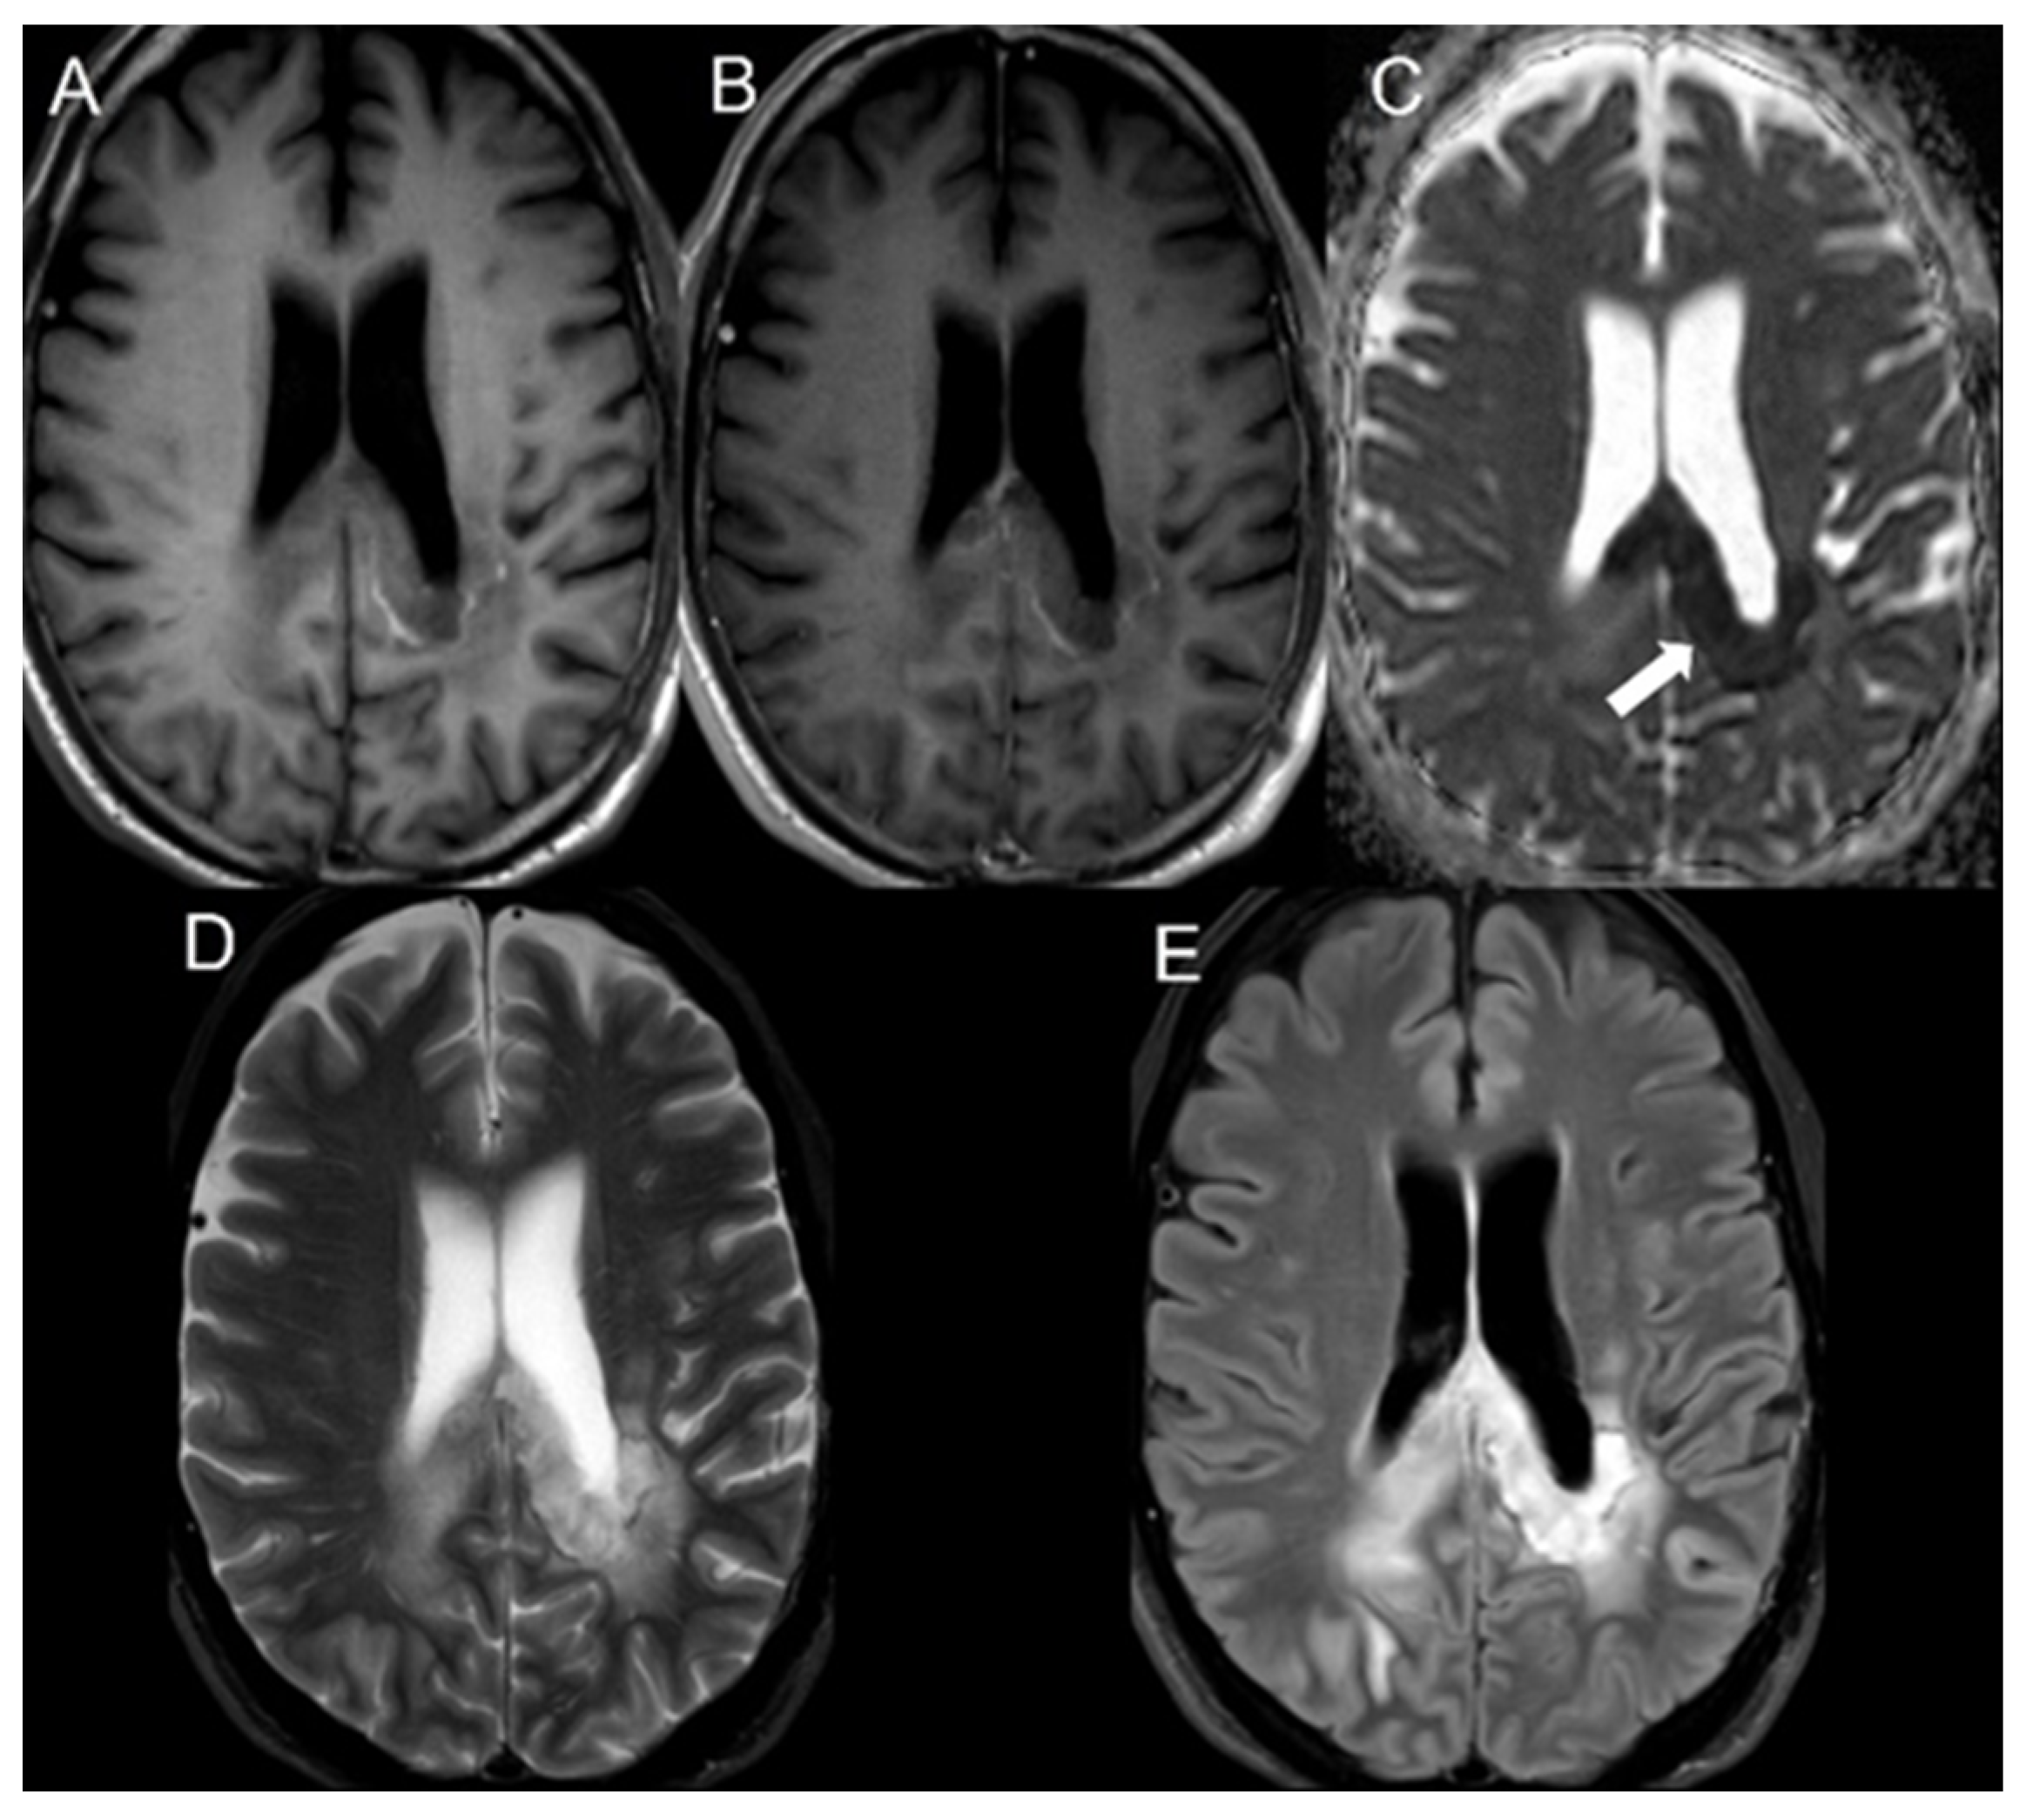

| Radiation necrosis | 58 | 479.0 ± 105.2 | 723.3 ± 64.0 | <0.001 |

| Radiation necrosis | 58 | 0.66 ± 0.14 |